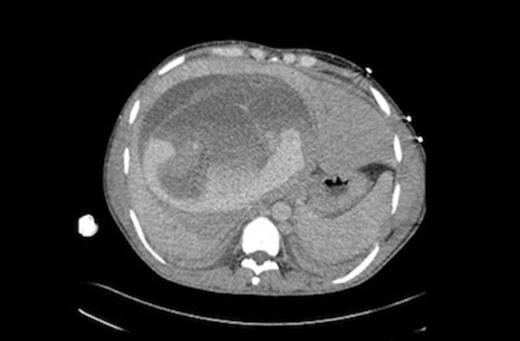

Repeat CT scan and angiography (Figures 1&2) revealed a 17cm mass occupying the right lobe of the liver with evidence of intrahepatic arterial and portal venous contrast extravasation. There was disruption of the normal right portal venous anatomy with the left portal vein being visible but displaced. Two arterial bleeding points were embolized. The underlying nature of the mass was unknown.

CT scan showing a large liver mass with associated haemorrhage. Detached laminated membrane is visualised.